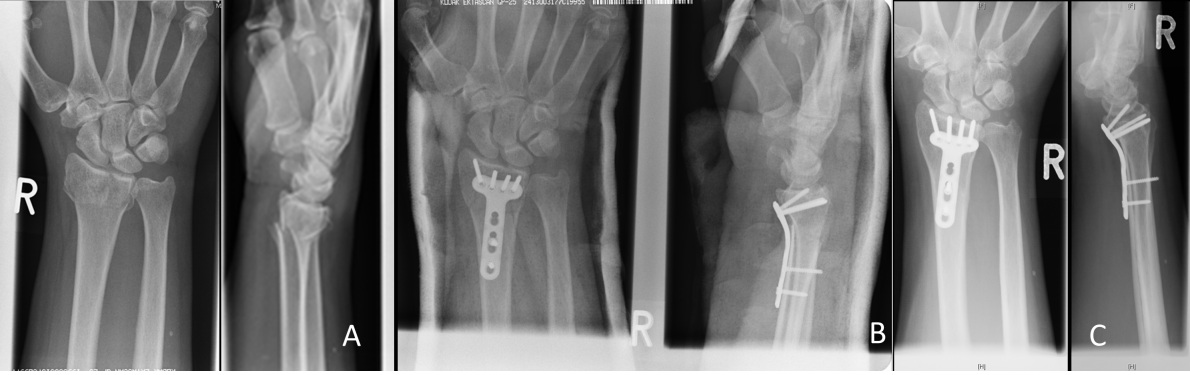

Figure 1: Radiographic follow-up series of a 46-year-old female patient with an AO 23C3 fracture, treated through a dorsal approach with 2.4 mm LCP (Synthes®). A) Postoperative x-ray with excellent reduction. B) Follow-up radiographs after 12 weeks. C) Follow-up radiograph one year after trauma with excellent radiological fracture consolidation and no significant loss of reduction.

Figure 2: Radiographic follow-up series of a 52-year-old female patient with an AO 23C2 fracture, treated through a volar approach with 2.4 mm LCP (Synthes®). A) Posttraumatic x-ray. B) Follow-up radiographs after 12 weeks. C) Follow-up radiograph 16 months after trauma with no major loss of reduction.